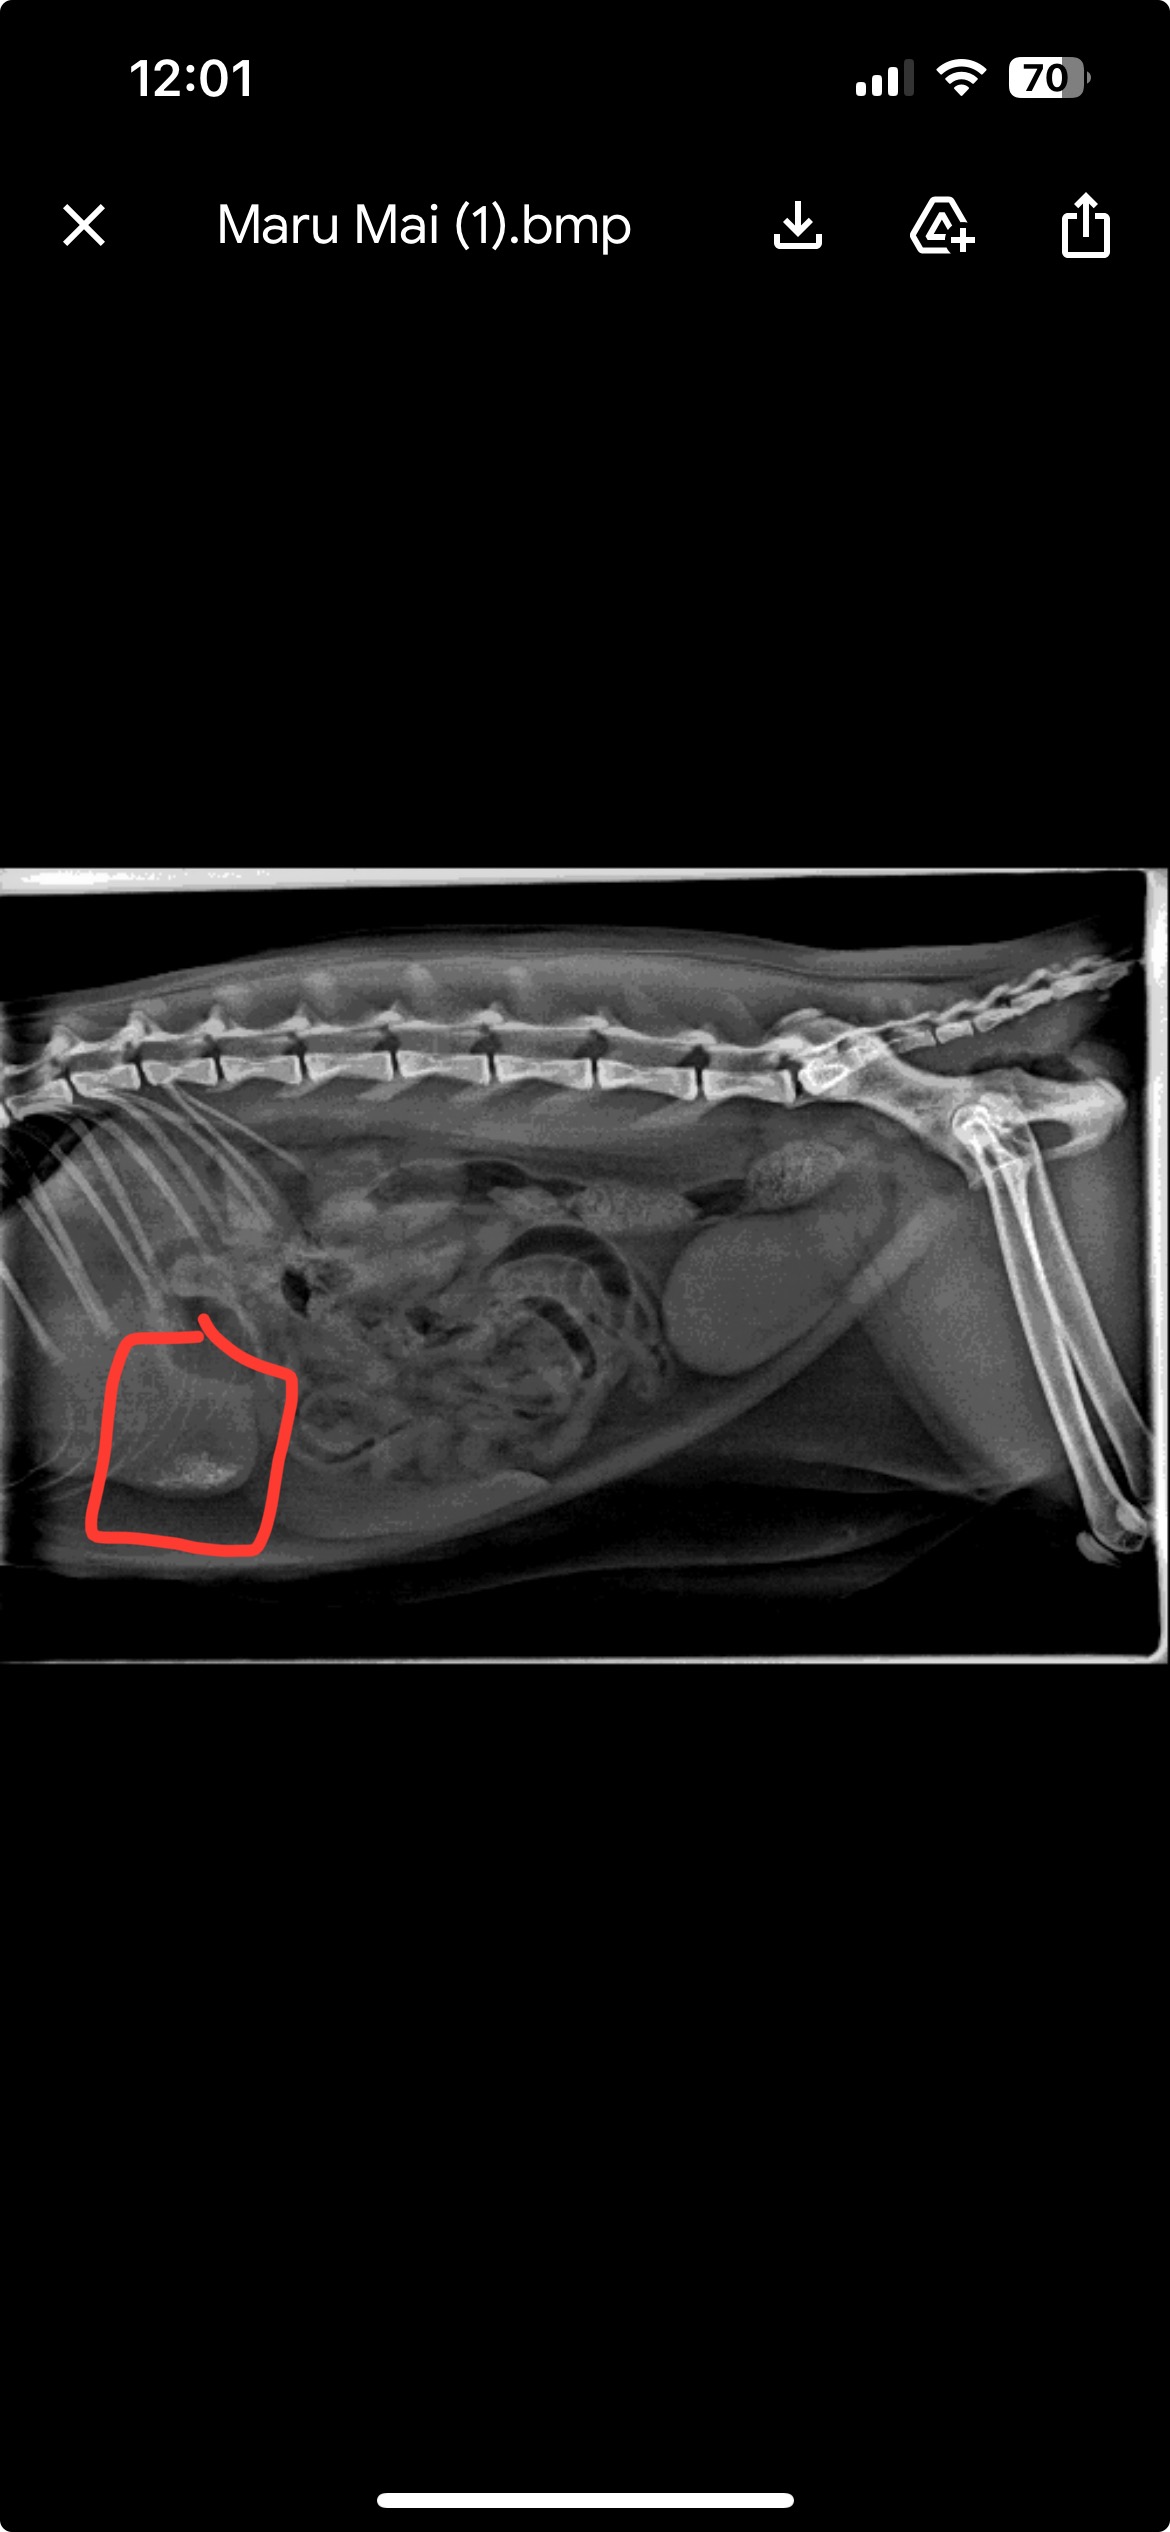

Hi, I’m trying to raise money to help fund intestinal surgery for my cat, Maru. She recently ingested a foreign object which has obstructed her stomach/intestines, requiring immediate surgery. As a university student I don’t have the means to cover an estimated $8000 medical bill without going into debt. Maru is a lovely and sweet girl, and is loved by many.

Please help me save her.